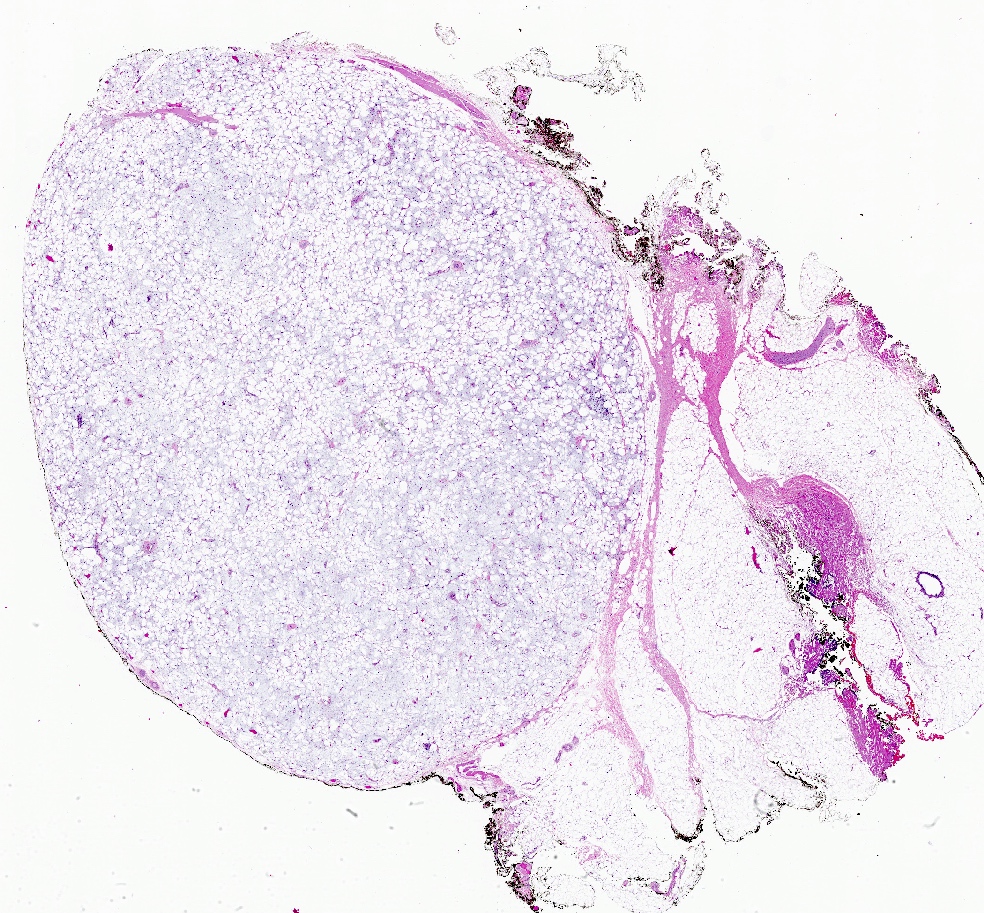

Gross description

- 2 mm to 15 cm, most cases not exceeding 3 cm (Arch Pathol Lab Med 2008;132:1813, Am J Surg Pathol 1994;18:1170)

- Well circumscribed, unencapsulated solid mass

- Firm, rubbery to gelatinous, whitish gray to pink nodular or whorled cut surface

Microscopic (histologic) description

- Well circumscribed, lacks true capsule, rarely infiltrative

Microscopic (histologic) images